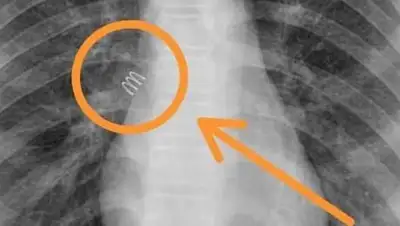

Пружина от шариковой ручки находилась в бронхах 11-летней девочки около года, передает zakon.kz.

Операция по извлечению металлической пружины от шариковой ручки размером два сантиметра длилась 40 минут, сообщает lada.kz.

Благодаря слаженной работе команды в составе детского хирурга областной детской больницы Орынбая Жалгасбаевича, одного из ведущих анестезиологов и ведущего эндоскописта многопрофильной клиники "SOFIE MEDGROUP" Роллана Елеусинова, из бронхов 11-летней пациентки после 11-месячного пребывания в бронхах была изъята металлическая пружина от шариковой авторучки длиною в два сантиметра. Состояние девочки стабильное, – сообщили в клинике "SOFIE MEDGROUP".